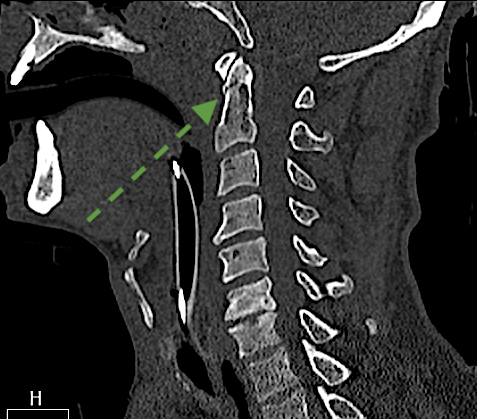

La reconstrucción sagital puede inducir a error al creer que la fractura (flecha verde) puede tratarse de manera conservadora ( tipo I)